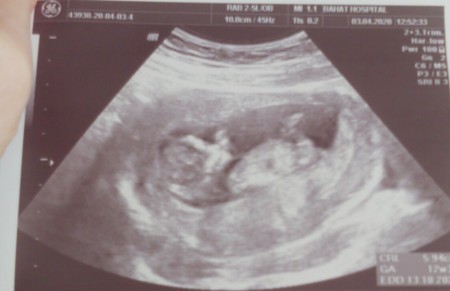

image

Buda benim bebiş canım 13 haftalık oldum